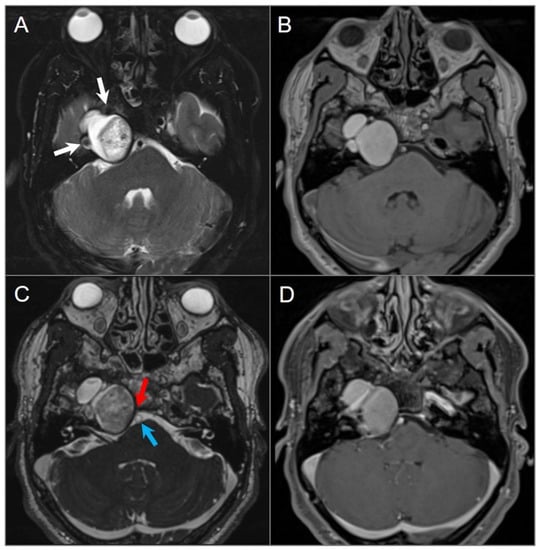

4.4.4. Endolymphatic Sac Tumor